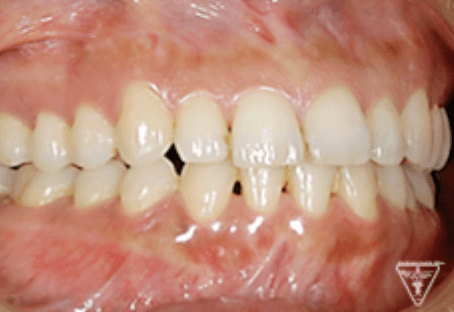

治療前後の比較